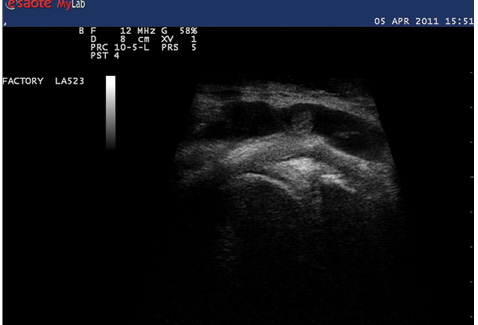

При оценке сонографического исследования пациентов, проведенного через 1 год от начала наблюдения, отмечались те же тенденции, что и в более ранний период наблюдения. Значительно снизилась частота выявления жидкости в суставной полости, особенно ее значительного накопления (у пациентов III градации) за счет более активного применения противовоспалительной терапии, включая пункцию кист Бейкера и интраартикулярные инъекции ГК. Также уменьшился удельный вес больных, у которых определяли допплеровские сигналы в синовиальной оболочке за счет значительного снижения частоты экспрессии I градации допплеровских сигналов. Сонографические изменения (рис. 1, 2) сопровождались клиническим эффектом: наблюдалось снижение значений индекса WOMAC (с 51,2±3,2 до 41,2±2,6; p<0,05), интенсивности боли по ВАШ (с 81,7±6,1 до 45,0±5,7; p<0,05), в то время как динамика лабораторных показателей была статистически недостоверной. Средние показатели СОЭ снизились с 7,5±4,7 до 5,5±1,6 мм/ч, а значения СРБ — с 4,3±2,7 до 3,6±2,2 мг/л (p>0,1). Результаты анализа динамики значений сонографических показателей группы больных ОАКС с активным синовитом свидетельствовали, что из 17 пациентов, отнесенных к этой группе в начале периода наблюдения, через 12 мес вышеописанным сонографическим критериям активного синовита соответствовали 14 (82,4%) пациентов. Еще один пациент присоединился к этой группе в связи с обострением синовита, ранее, при первом исследовании, у него наблюдалось лишь незначительное утолщение синовиальной оболочки до 3 мм с единичными точечными допплеровскими сигналами и отсутствие жидкости в полости сустава. Лечение этих пациентов в продолжение 1-годичного периода наблюдения потребовало применения НПВП в течение большего количества времени по сравнению с остальными больными: в среднем 174,3 суточных дозировок против 56,4 (за суточную дозу нимесулида принята доза 100 мг, мелоксикама — 7,5 мг, ибупрофена —1200 мг, диклофенака — 75 мг).

Рис. 1

Сонографические признаки синовита: утолщение синовиальной оболочки, свободная жидкость в заднем завороте суставной полости